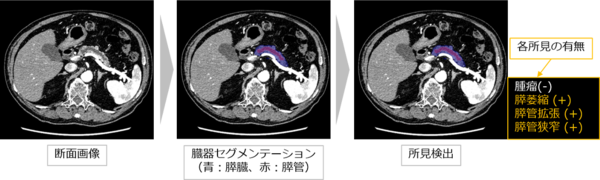

腫瘤(直接所見)および膵管拡張・膵管狭窄(間接所見)を検出した症例(ステージ1)

富士フイルムと神戸大学は,CT画像から膵臓がんの早期発見を支援するAI技術の開発を目指し,2021年8月より,神戸大学大学院医学研究科の児玉 裕三教授・村上 卓道教授を中心としたチームのもとで共同研究を進めている。今回,膵臓がん患者を含む約1,000症例の造影CT画像をAIに学習させ,腹部の造影CT画像から膵臓がんが疑われる所見を検出する技術の開発に成功した。本技術は,膵臓がんの直接所見である腫瘤のみならず,間接所見である膵萎縮・膵管拡張・膵管狭窄などを検出する。本技術を活用して医師の負担を軽減することで,より精度の高い診断につながることが期待できる。